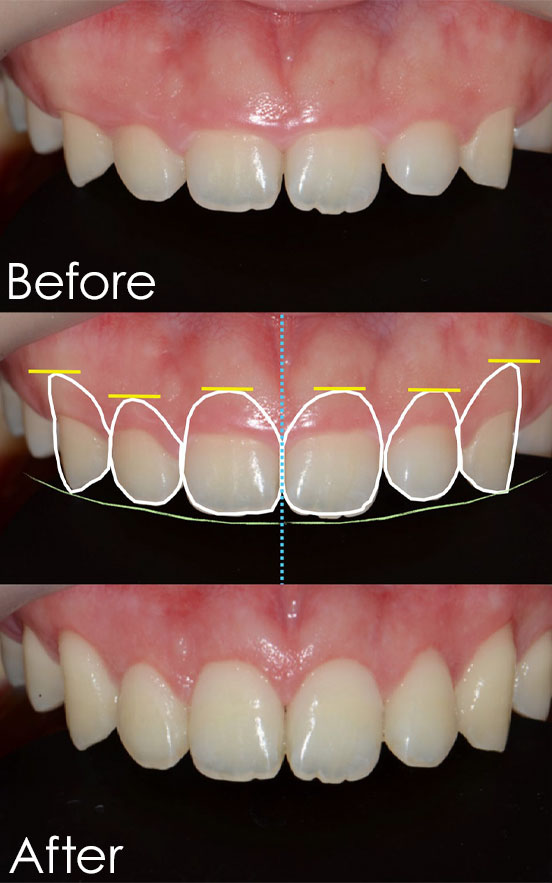

男性(30代)

お悩み:前歯を綺麗にしたい

治療内容:前歯の審美治療(歯茎の整形とジルコニアオールセラミック)

治療期間:2週間

治療回数:4回(歯茎の整形と抜糸、型取りとセット)

金額:歯茎の整形 27,500円/本×3(税込)

ジルコニア 143,000円/本×6(税込)

リスク・副作用:歯を削る、腫れる可能性、痛みが出る可能性がある